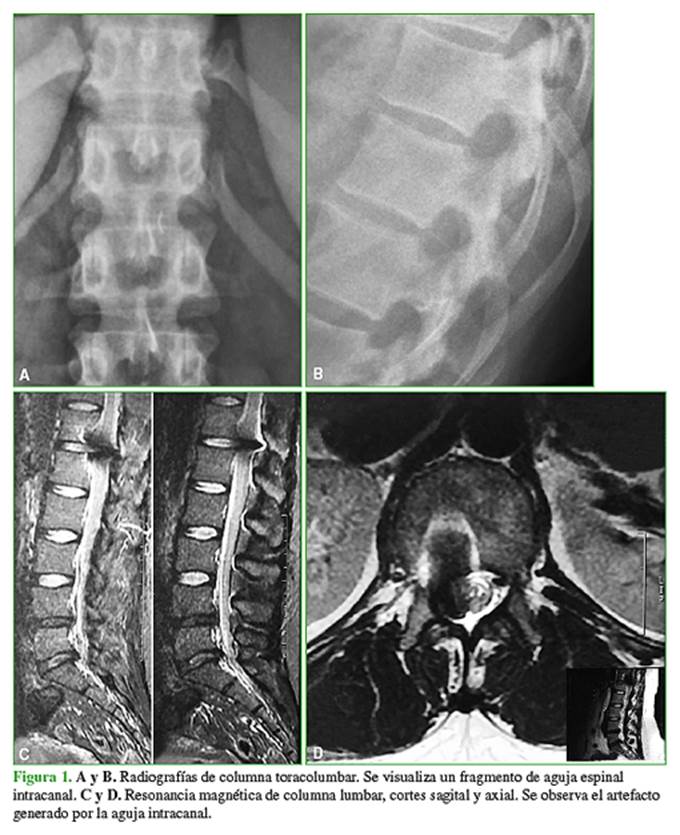

La cirugía se llevó a cabo con potenciales evocados somatosensitivos y motores, y no se observaron alteraciones. Luego de la extracción, se realizaron estudios por imágenes con el fin de comprobar y documentar la ausencia del fragmento de aguja (Figura 3).

A las 48 h de la cirugía, se le permitió la deambulación. La paciente manifestó dolor en la zona de la herida quirúrgica que tuvo una buena respuesta a los analgésicos. No tenía dolor de proyección radicular derecho como antes de la cirugía (puntaje 0/10 en la escala analógica visual). Al tercer día posoperatorio, se le dio el alta médica, se le indicaron cuidados iniciales durante la primera semana y, luego del retiro de los puntos, a los 10 días, se le permitió una vida normal. En la actualidad, con 24 meses de seguimiento, la paciente no tiene síntomas.